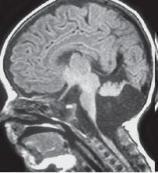

• 室管膜瘤

室管膜瘤來源于腦室與脊髓中央管的室管膜細胞或腦內白質室管膜細胞巢的中樞神經系統腫瘤。男多于女,多見于兒童及青年。疾病描述室管膜瘤來源于腦室與脊髓中央管的室管膜細...